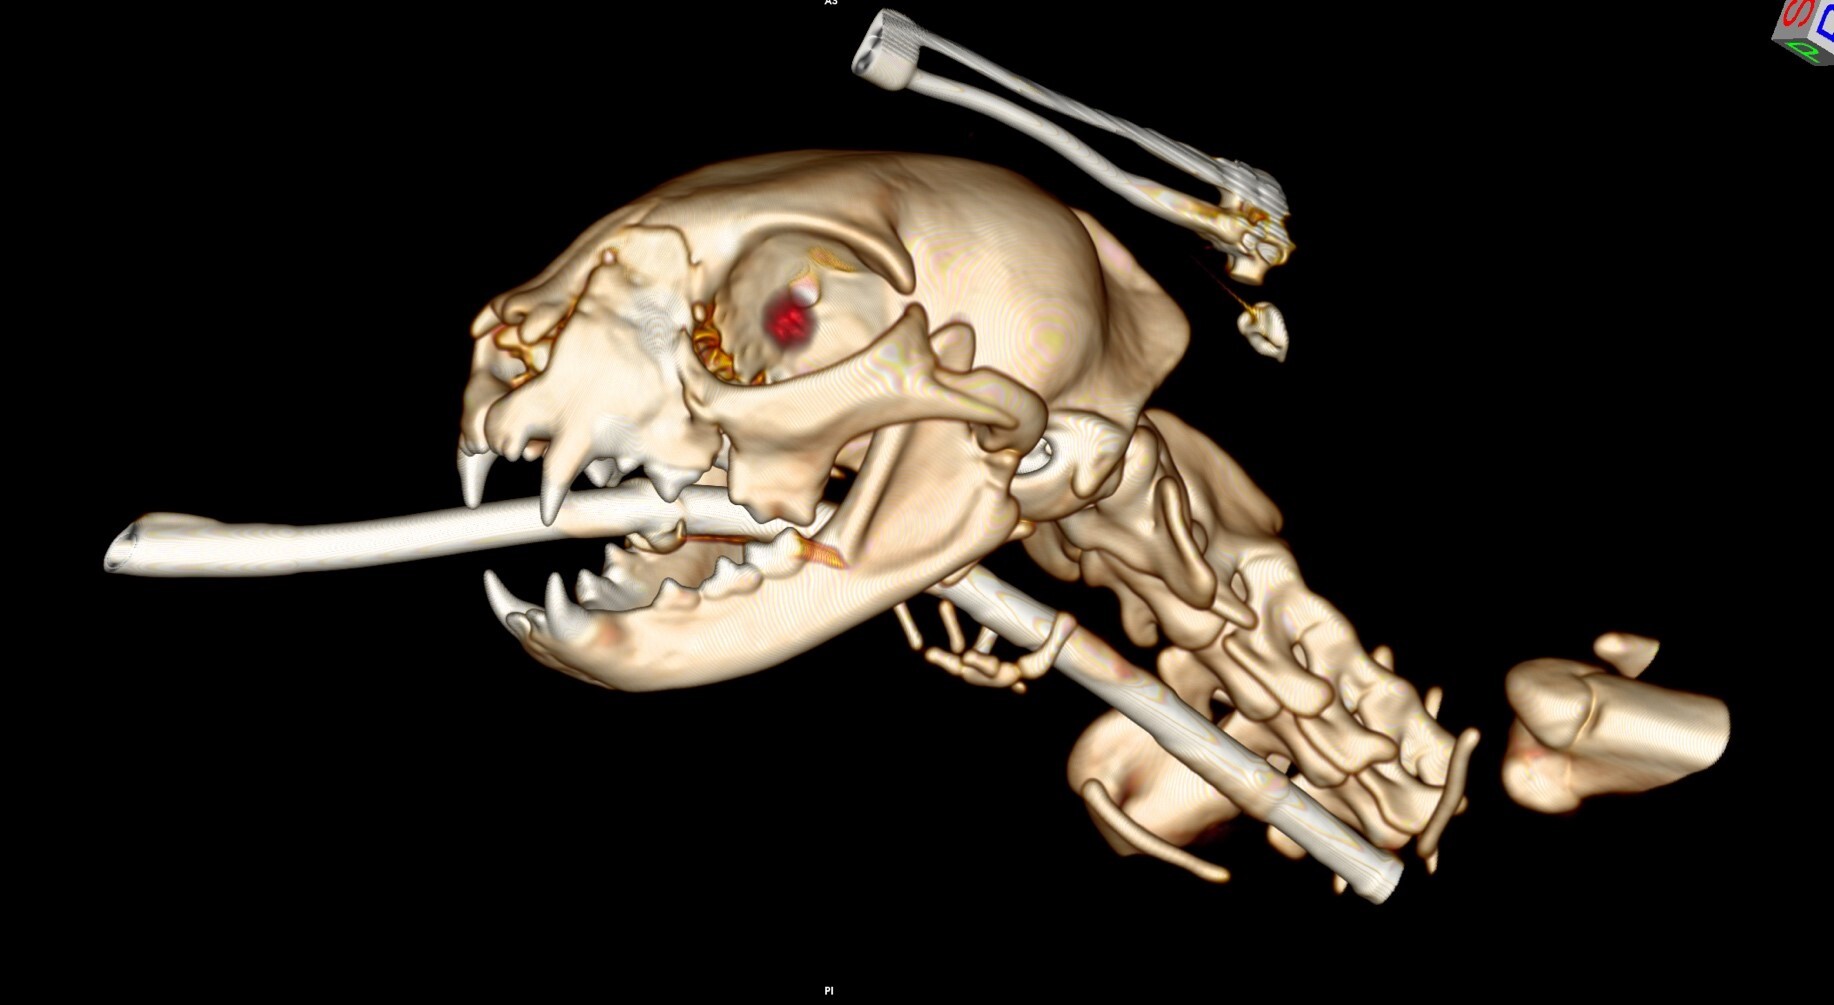

症例②:交通事故による顔面多発骨折

| 種類 | 猫 ミックス |

|---|---|

| 年齢 | 1歳(当時) |

| 主訴 | 外から帰ってきたら、顎から出血をしているとのことで来院 |

*手術中の写真を掲載しております。苦手な方はご注意ください。

はじめにレントゲン検査を行いました。頭部以外に外傷はないか胸部も撮影しました。

頭部CT画像(3Dデータ)

CT検査の結果、顔面を複数箇所骨折していることがわかりました。レントゲン検査でははっきりとしない複雑な骨折も、CT検査ではこのように立体的に画像を構築することができるため、より損傷部の状態を把握することが可能です。

ワイヤー等を用い、CT画像を活用しながら整復術を行いました。